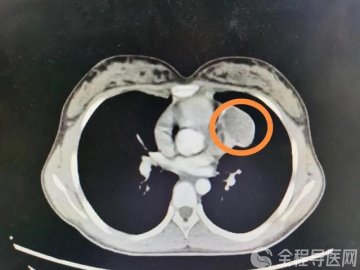

据介绍,小儿遗尿症在临床上是一种比较常见的泌尿系统功能性疾病。一般发病年龄在5岁以上,睡眠状态下每周不自主排尿≥2次,持续3个月以上,睡眠较深,不易唤醒,小便常规实验室检查无异常,部分患儿腰椎X线检查发现隐性脊柱裂,可诊断为小儿遗尿症。